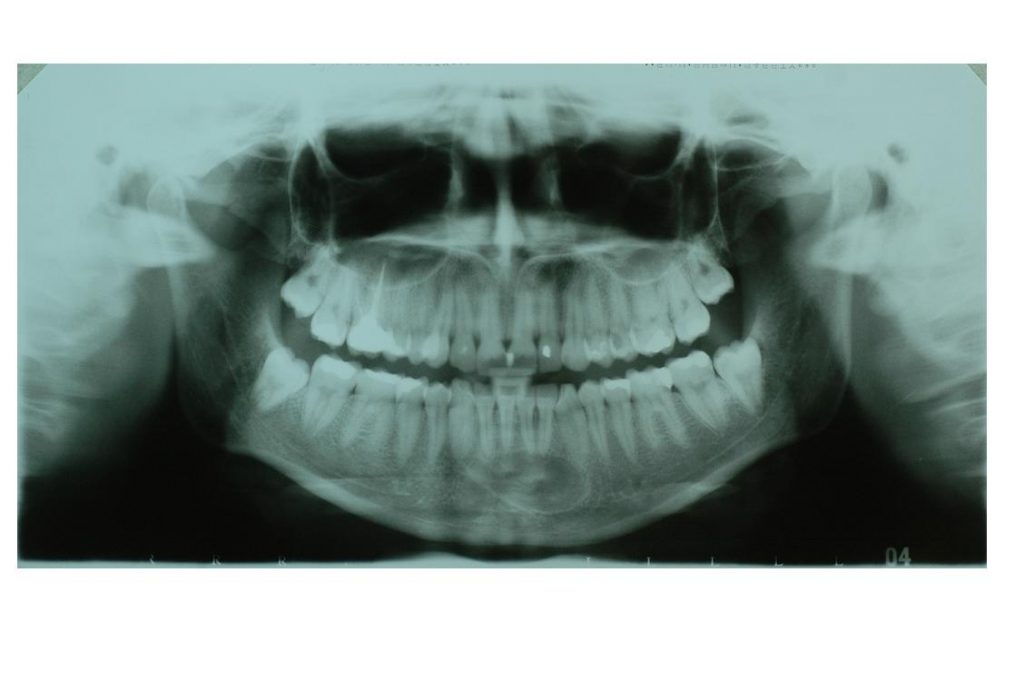

- Celem pracy jest przedstawienie opisu przypadku torbieli samotnej w żuchwie w jej przednim odcinku u 19-letniej pacjentki, którą zdiagnozowano przypadkowo po wykonaniu zdjęcia panoramicznego zębów.

Streszczenie: Torbiel samotna (SBC – solitary bone cyst) jest łagodną zmianą, często wykrywaną w obrębie kości długich u dzieci, w pierwszej i drugiej dekadzie życia. Przy lokalizacji w kościach twarzoczaszki najczęściej umiejscowiona jest w odcinku bocznym żuchwy. Celem pracy jest przedstawienie opisu przypadku torbieli samotnej w żuchwie w jej przednim odcinku u 19-letniej pacjentki, którą zdiagnozowano przypadkowo po wykonaniu zdjęcia panoramicznego zębów.

Summary: The solitary bone cyst (SBC) is a benign lesion, often found in the long bones of children, in the first and second decades of life. Its most common location in the jaw bones is the posterior region of the mandible. The aim of the paper is to present a case report of a solitary bone cyst in the frontal section of the mandible in a 19-year-old patient, which was diagnosed accidentally after a panoramic X-ray was done.